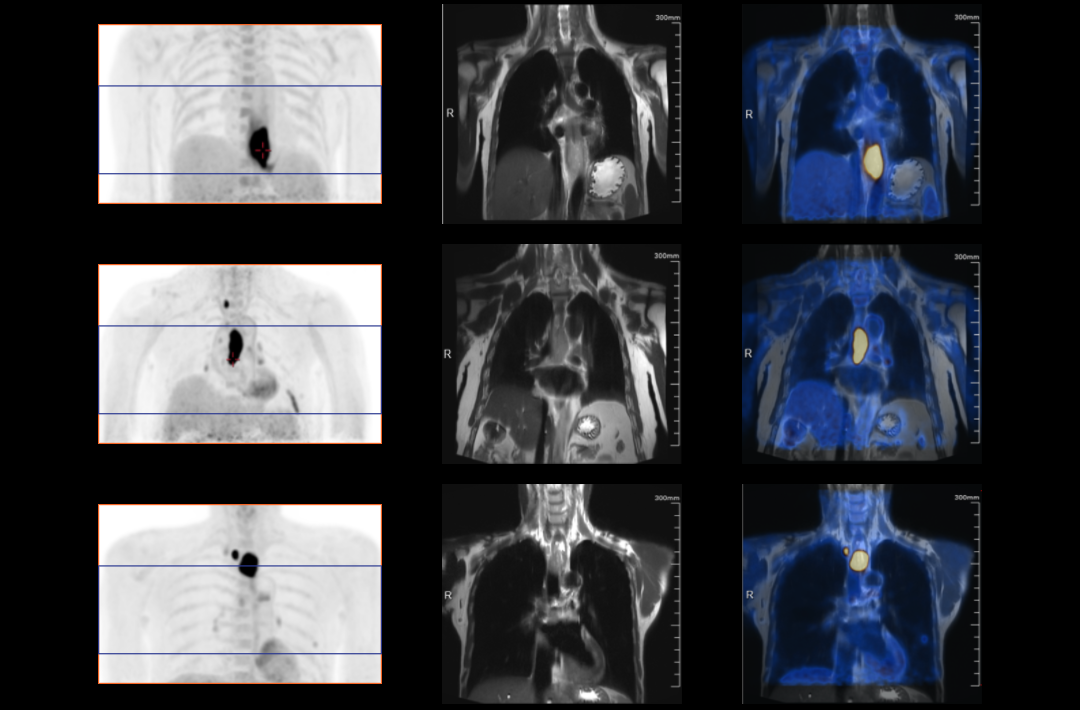

The following are the cases of optimized TNM staging of breast cancer, esophageal cancer, prostate cancer and other diseases under the long axial field of "spatio-temporal integration" ULTRA-clear TOF PET/MR. Thanks to Capital Medical University Xuanwu Medical Treatment for providing the image.